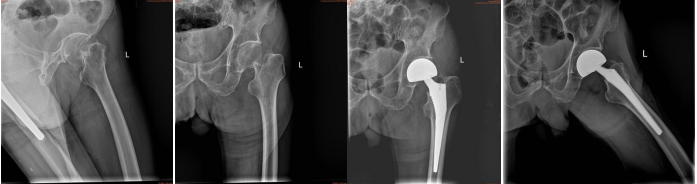

89岁吴某(本院病例)左股骨颈骨折后,骨科团队5天内完成人工关节置换术,术后3天实现助行器行走。针对老年患者谵妄高发问题,科室创新采用“家属协同镇痛管理”,使术后谵妄发生率较传统模式下降42%。